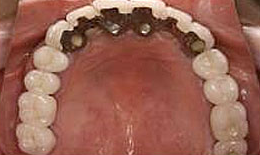

インプラント症例(1)30代 女性

治療後

上顎

保存困難な歯を抜歯後、インプラントを7本埋め込み、セラミックスクラウンを被せた

上部構造

(メタルボンドクラウン)18本

155,000×18=2,790,000円(税抜)

右上

メタルボンドブリッジ

90,000×4=360,000円(税抜)